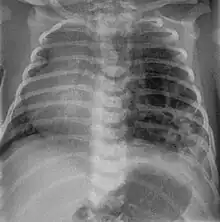

| Left tension pneumothorax with a large, well-demarcated area devoid of lung markings with tracheal deviation and movement of the heart away from the affected side. |

Tension pneumothorax

Tension pneumothorax is an emergent condition in which air gets trapped in the space between the chest wall and the lung. This space is referred to as the pleural space. Because air can't escape from this space, the pocket of air grows larger and larger which results in collapse of the lung closest to the pneumothorax. Forces are transmitted to the mediastinum and effectively "push" the mediastinal structures to the opposite side of the chest. [5]